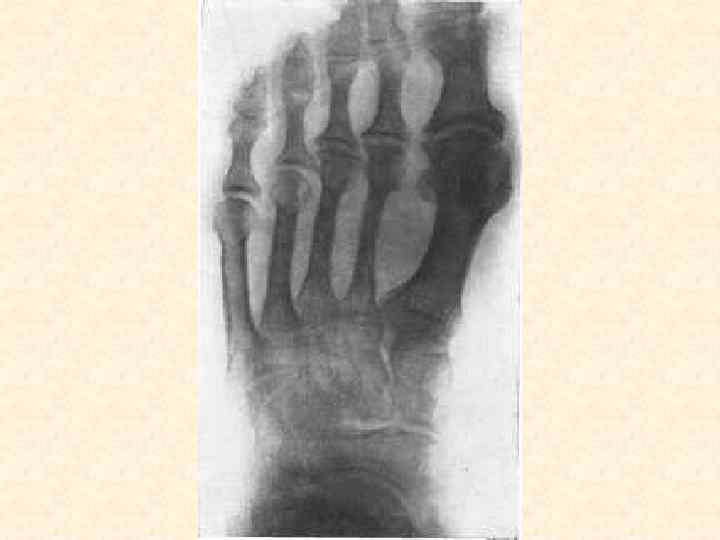

Заболевания, поражающие костную систему • • • Остеомиелит, артрит Артроз Остеопороз Остеомы Переломы костей

Методы диагностики поражения опорной системы человека 1. 2. 3. 4. Рентген, КТ, Радиоизотопная диагностика, Остеоденситометрия